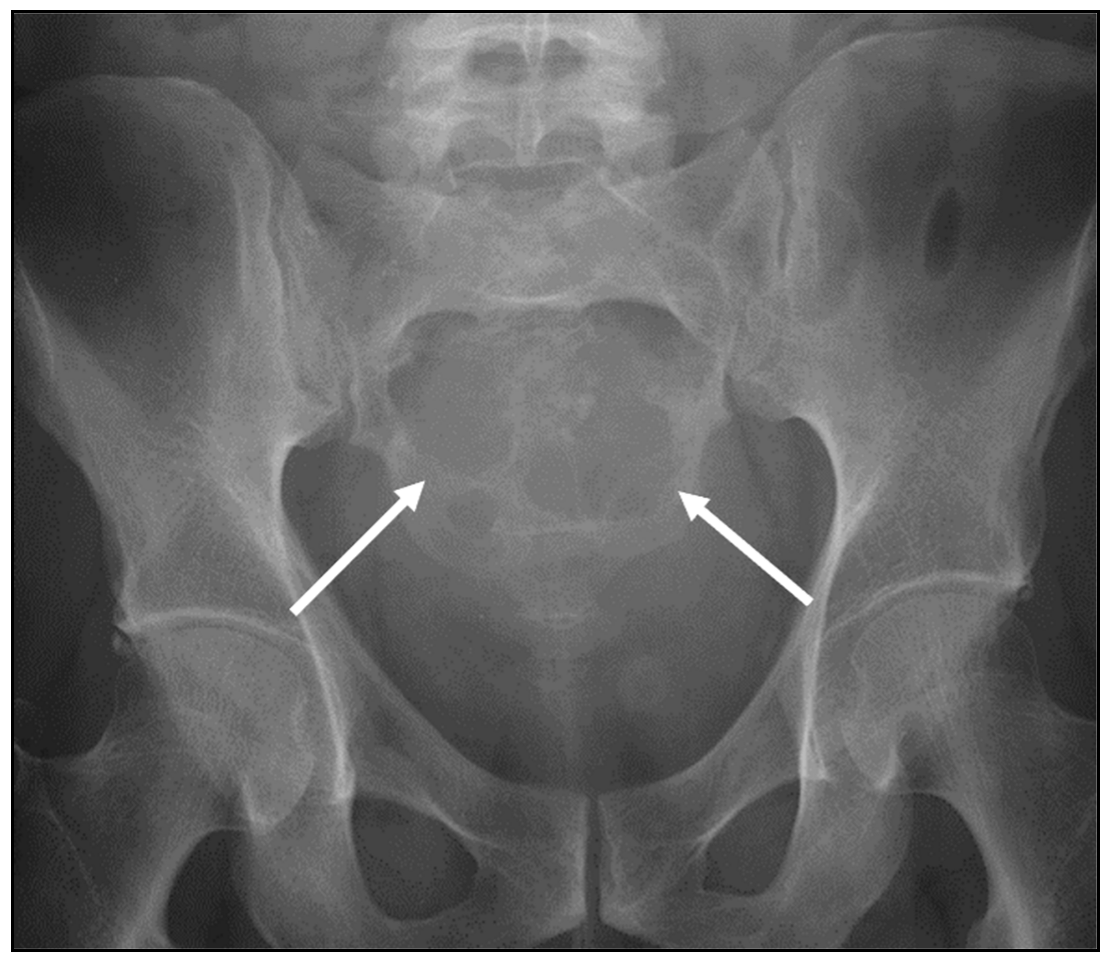

| Plasmacytoma | Lytic and destructive, vertebral collapse. Soap bubble appearance. | Low to intermediate signal on T1 and increased signal on fluid-sensitive sequences and enhancement post-contrast. Extra-osseous soft tissue component. Multiple trabeculae within the lesion, with a characteristic soap bubble appearance. |